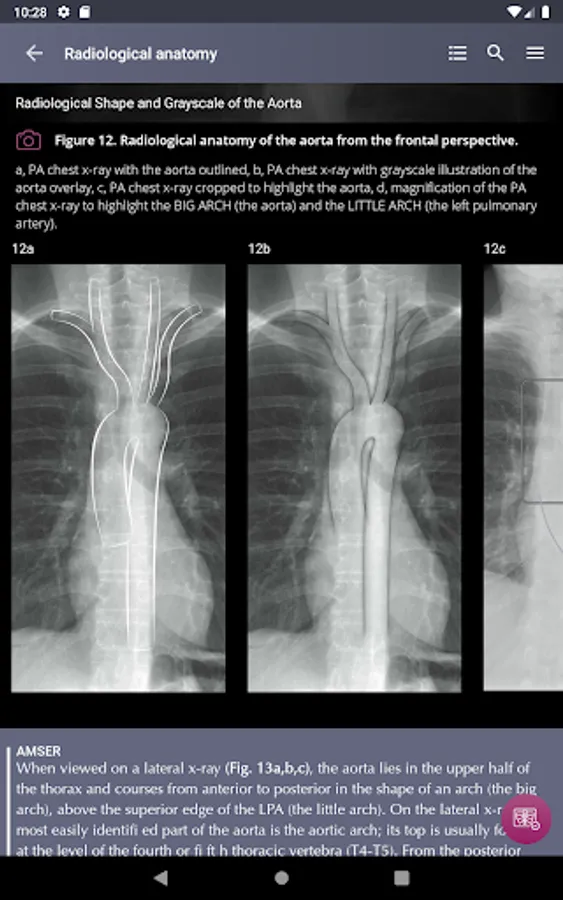

Radiological Anatomy – Descriptions of various anatomical structures as they would appear on PA and lateral chest x-rays.